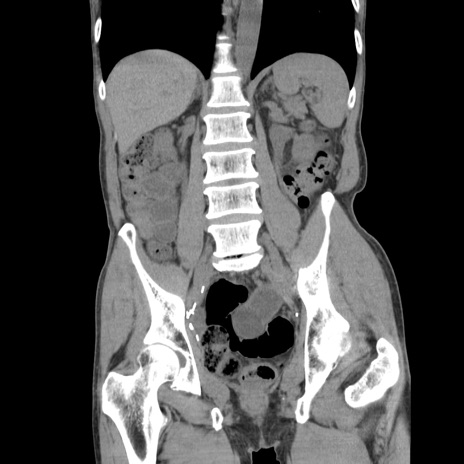

症例11(冠状断像)

【症例】 60歳代男性

【主訴】 下腹部痛

【現病歴】 本日夜中より下腹部痛の症状認め、受診。

【既往歴】 膀胱癌(膀胱全摘+尿管皮膚瘻術) 、胃癌術後

【身体所見】 BT 35.3℃、PR 58/min、BP 136/98mHg、腹部平坦、軟、腸蠕動音±、ストマ留置あり、左上腹部~正中部に圧痛あり、反跳痛なし。

【データ】WBC 5100、CRP0.01